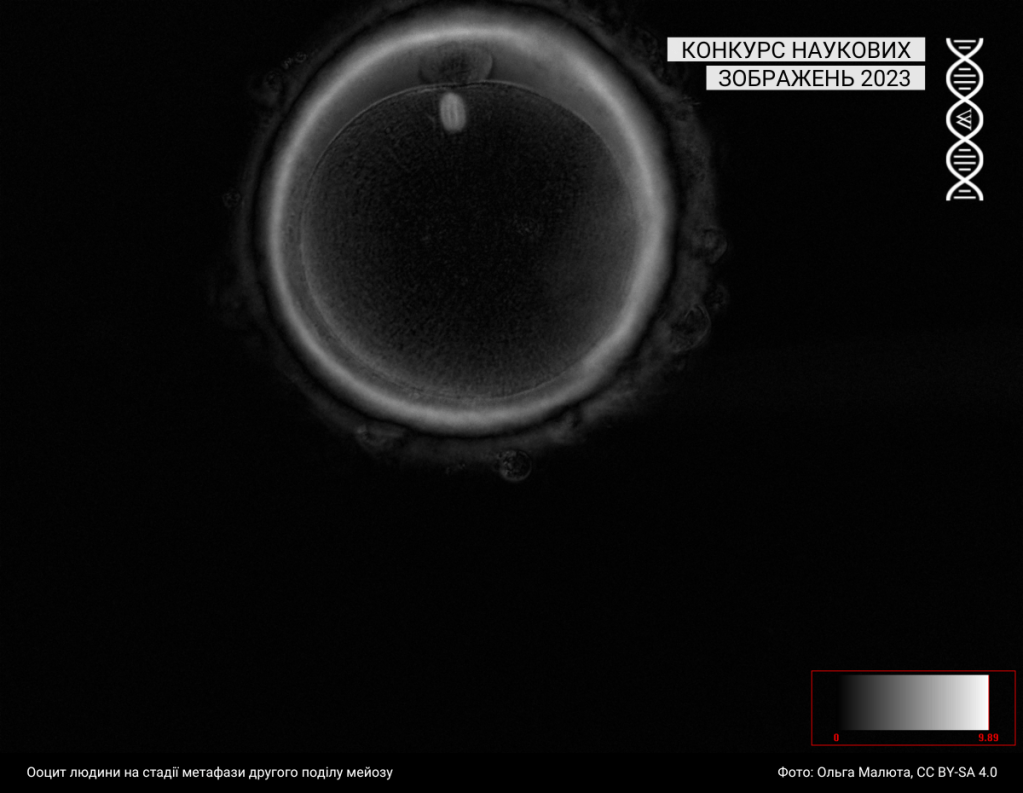

Під цю категорію підпадають світлини, зроблені за допомогою різних методик мікроскопії. Минулого року до цієї категорії учасники та учасниці завантажили 43 фотографії.

Спеціальна відзнака журі

Журі призначили спеціальну відзнаку серії зображень однієї авторки: https://w.wiki/99qJ, https://w.wiki/99qK, https://w.wiki/99qL, https://w.wiki/99qM